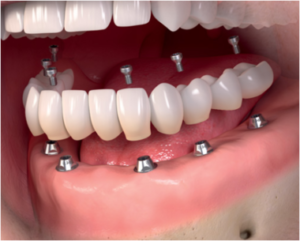

Які варіанти протезування існують при адентії – повній відсутності зубів? Найбільш надійний і ефективний як з функціональної, так і з естетичної точки зору, варіант протезування – установка «незнімніка» на 6-8 імплантатах (класичний варіант – на 8 імплантатах, більш економічний – «All-on-6» – на 6 імплантатах) . Існує також технологія протезування за технологією «All-on-4» ( «все на 4»), коли в якості опори для протеза використовується всього 4 імпланта. На них можна встановити як знімний, так і незнімний протез, хоча, звичайно ж, конструкція «незнімніка» на 4 опорах буде менш надійною і стабільною, ніж на 6 або 8. Існує також надекономічний варіант знімного протезування – всього лише на 2-3 імплантатах , їх буде цілком достатньо для надійної фіксації «знімача».

Для незнімного повного протезування зубів на імплантатах потрібно встановити від 6 до 8 імплантів – опор. При необхідності проводиться аугментація (нарощування) кісткової тканини ( синус – ліфтинг ) в окремих передбачуваних ділянках імплантації імплантів.